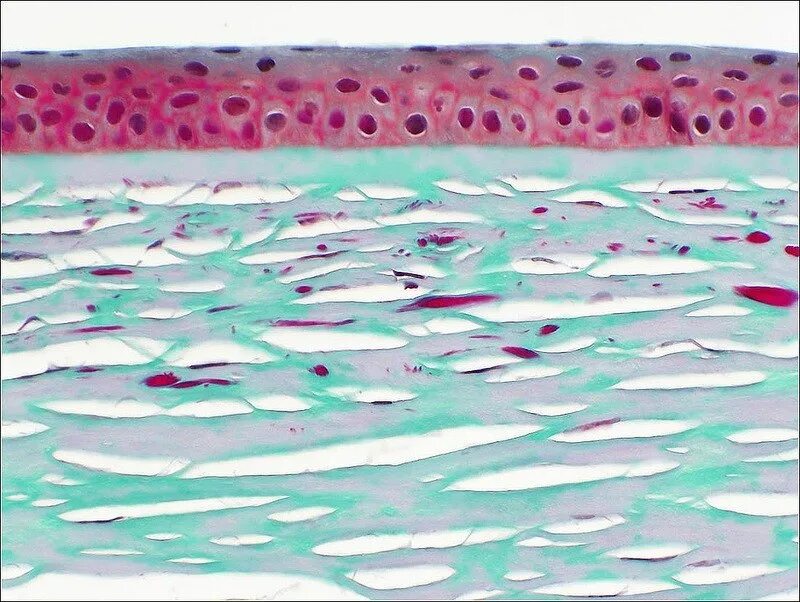

Окрашивание гистологического препарата